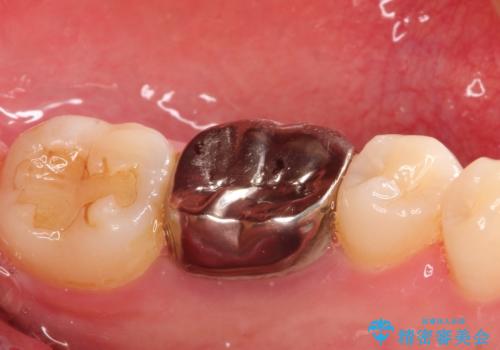

- 下の奥歯の銀歯を白くしたいとのことで来院されました。

痛みなどの症状はなく、前に根管治療を行っている歯になります。

古い銀歯を除去し、審美性の良いセラミッククラウンでの治療を行うこととしました。